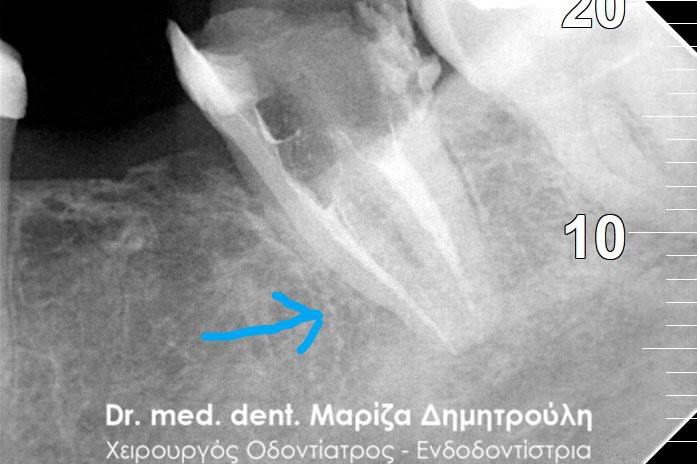

Περιστατικό – Επανάληψη απονεύρωσης και προσθετικής

Η ασθενής παρουσιάστηκε στο ιατρείο με την επιθυμία να ξανακολληθούν οι στεφάνες της στους δυο κάτω αριστερούς προγομφίους, γιατί τον τελευταίο καιρό της αισθανόταν “λίγο χαλαρές”.

Η κλινική εξέταση των δοντιών έδειξε κάτι πιο πολύπλοκο απ΄ αυτό που περιέγραφε η ασθενής. Οι στεφάνες ήταν πράγματι χαλαρές και δεν προσάρμοζαν πάνω στα δόντια, γιατί τα δόντια κάτω από τις στεφάνες είχαν επανατερηδονιστεί.

Η ακτινογραφική εξέταση αποκάλυψε ότι και τα δύο δόντια είχαν απονευρωθεί στο παρελθόν, έφεραν το καθένα στο εσωτερικό χυτό μεταλλικό άξονα και στο ακρορρίζιο διαπιστώθηκε μια περιακρορριζική αλλοίωση. Η αλλοίωση αυτή μαρτυρά τη φλεγμονή του δοντιού στο άκρο της ρίζας.

Μετά από συνεννόηση με την ασθενή αποφασίστηκε το παρακάτω σχέδιο θεραπείας:

1. Αφαίρεση των παλιών στεφανών (θηκών δοντιού)

2. Αφαίρεση του χυτού μεταλλικού άξονα από το εσωτερικό του ριζικού σωλήνα

3. Επανάληψη της απονεύρωσης

Αφού ολοκληρώθηκαν οι παραπάνω εργασίες πραγματοποιήθηκε αποκατάσταση των δοντιών με άξονες υαλονημάτων και κατασκεύη καινούριων στεφανών. Οπώς φαίνεται και στην τελική ακτινογραφία 6 μήνες μετά την διεκπεραίωση του σχεδίου θεραπείας η φλεγμονή στο ακρορρίζιο του δοντιού είχε ήδη υποχωρήσει.

ΠΡΙΝ

Έλεγχος αφαίρεσης άξονα και παλιάς απονεύρωσης

Τελική ακτινογραφία